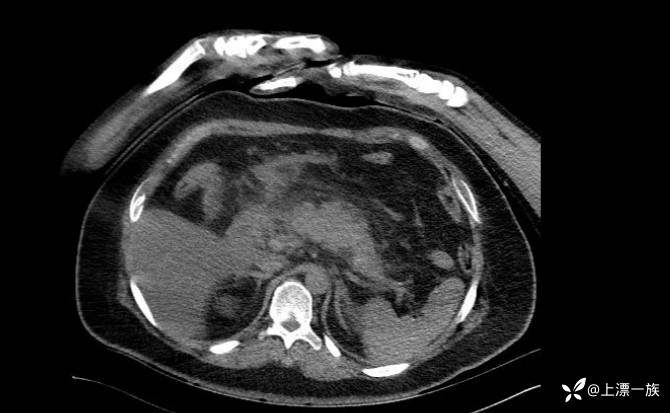

当天腹部CT